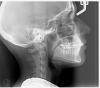

Marina87 Опубликовано 6 июля, 2013 Автор Поделиться Опубликовано 6 июля, 2013 Вот фото Ссылка на комментарий